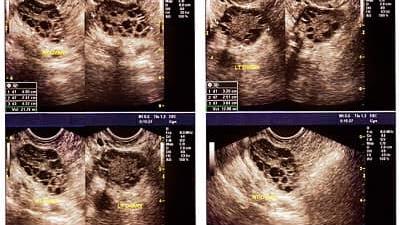

تخمدانهای پلی کیستیک سه فاکتور دارد که شامل تخمدانهای پر کیست، قاعدگی نامنظم و موهای زائد صورت میشود.ممکن است فردی تخمدان پلی کیستیک داشته باشد ولی دو نشانه دیگر را نداشته باشد. معمولا باید بهدنبال قاعدگی نامنظم و موهای زائد به پزشک مراجعه کرد. ما انتظار داریم در سنین اول پس از بلوغ قاعدگیها نامنظم باشد، ولی از سنین ۱۶ تا ۱۷ سال به بعد بروز قاعدگی نامنظم باید از حیث تخمدان پلی کیستیک بررسی شود.